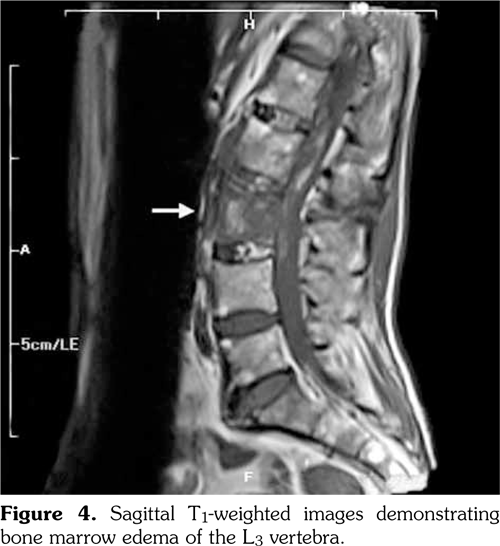

A 61-year-old man was admitted to the department of neurosurgery with bilateral lower extremity weakness which had begun suddenly. The patient had a history of spontaneous falls at home on the same day. He soon developed back pain and weakness in his lower extremities. Magnetic resonance imaging (MRI) of the lumbar spine revealed L2 vertebral fracture and epidural hematoma extending from L2 to L4. The patient underwent decompression surgery for the epidural hematoma. After the surgery, the patient was consulted in our clinic to establish a rehabilitation program. There was a minor trauma in his history two weeks ago, and an ischemic stroke two years ago. The patient reported neck and back pain ongoing for many years, and morning stiffness lasting for 30 minutes. There was no history of night pain, arthritis, skin lesions or inflammatory bowel disease. Upper limb motor strength was normal. Lower limb motor strength examination revealed that bilateral hip flexor and knee extensor strength was 3/5, ankle dorsiflexor strength was 4/5, bilateral toe dorsiflexor strength was 3/5, extensor digitorum brevis muscle strength was 3/5, and ankle plantar flexor strength was 5/5. Sensorial examination was normal. Hoffman, Achilles clonus, and Babinski signs were positive bilaterally. There was no urinary or bowel incontinence. Lumbosacral and sacroiliac joint radiographies were compatible with bilateral grade IV sacroiliitis, syndesmophytes, squared vertebral bodies, and “bamboo spine” formation. Furthermore, radiography revealed anteriorposterior longitudinal ligament calcification and scoliosis (Figure 1, 2).